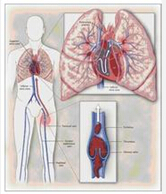

肺栓塞和下肢静脉血栓

疾病介绍:肺栓塞、肺动脉高压肺栓塞(pulmonary embolism, PE)是以各种栓子阻塞肺动脉系统为其发病原因的一组疾病或临床综合征的总称,以下肢静脉血栓脱落引起…【详细】

肺栓塞和下肢静脉血栓

疾病介绍:肺栓塞、肺动脉高压肺栓塞(pulmonary embolism, PE)是以各种栓子阻塞肺动脉系统为其发病原因的一组疾病或临床综合征的总称,以下肢静脉血栓脱落引起…【详细】

肺栓塞和下肢静脉血栓

疾病介绍:肺栓塞、肺动脉高压肺栓塞(pulmonary embolism, PE)是以各种栓子阻塞肺动脉系统为其发病原因的一组疾病或临床综合征的总称,以下肢静脉血栓脱落引起…【详细】

肺栓塞和下肢静脉血栓

疾病介绍:肺栓塞、肺动脉高压肺栓塞(pulmonary embolism, PE)是以各种栓子阻塞肺动脉系统为其发病原因的一组疾病或临床综合征的总称,以下肢静脉血栓脱落引起…【详细】

肺栓塞和下肢静脉血栓

疾病介绍:肺栓塞、肺动脉高压肺栓塞(pulmonary embolism, PE)是以各种栓子阻塞肺动脉系统为其发病原因的一组疾病或临床综合征的总称,以下肢静脉血栓脱落引起…【详细】

肺栓塞和下肢静脉血栓

疾病介绍:肺栓塞、肺动脉高压肺栓塞(pulmonary embolism, PE)是以各种栓子阻塞肺动脉系统为其发病原因的一组疾病或临床综合征的总称,以下肢静脉血栓脱落引起…【详细】

肺栓塞和下肢静脉血栓

疾病介绍:肺栓塞、肺动脉高压肺栓塞(pulmonary embolism, PE)是以各种栓子阻塞肺动脉系统为其发病原因的一组疾病或临床综合征的总称,以下肢静脉血栓脱落引起…【详细】